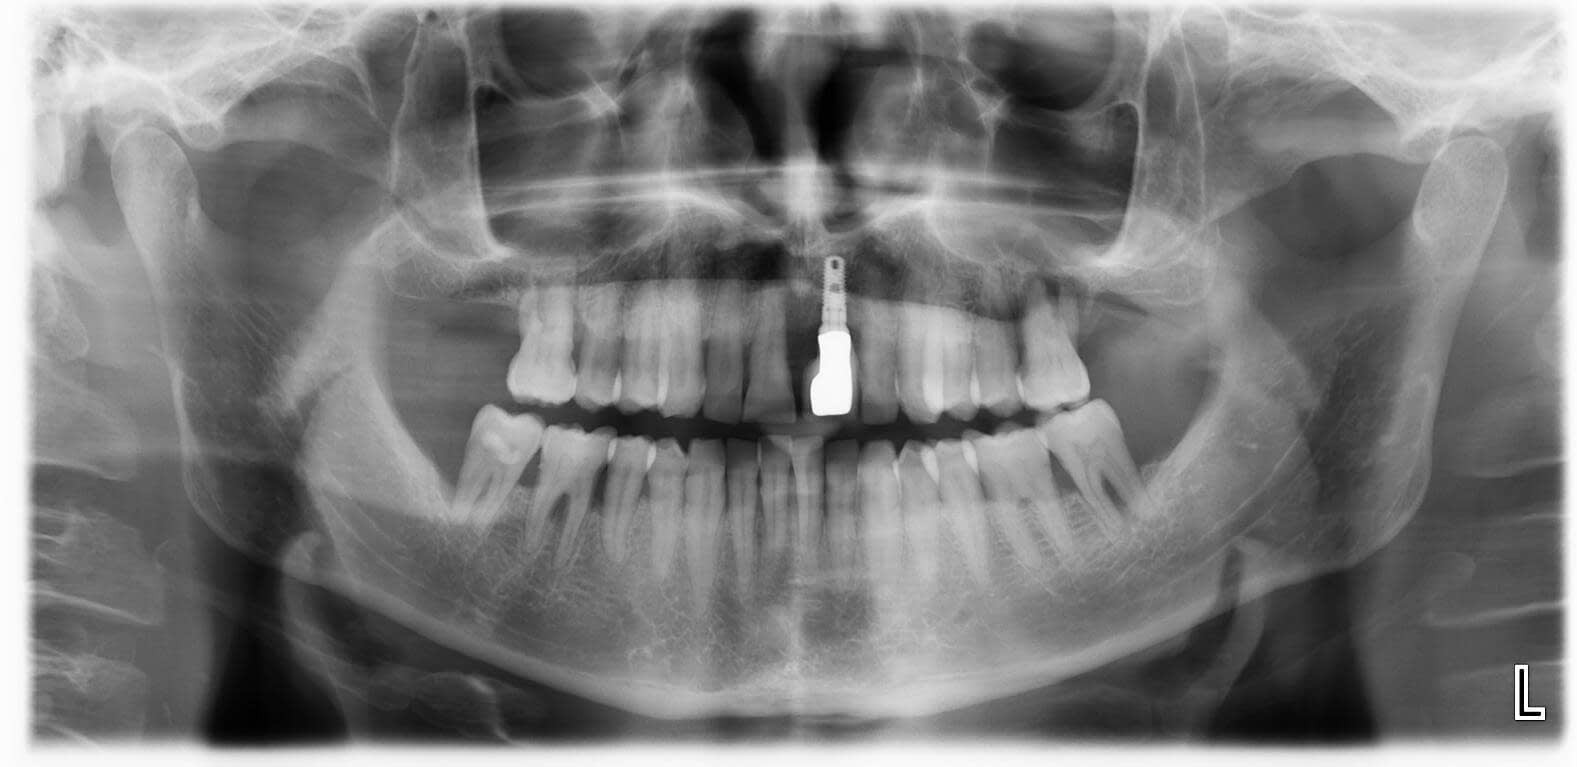

El radiodiagnóstico es una herramienta de vital importancia en el día a día de una clínica dental, ya que a través de ella podemos obtener una imagen certera y pormenorizada de la zona maxilofacial del paciente.

Gracias a esta tecnología, podemos valorar con precisión el estado de la boca y detectar con mayor claridad diferentes situaciones clínicas, como piezas afectadas, procesos infecciosos o tratamientos previos que requieren seguimiento.